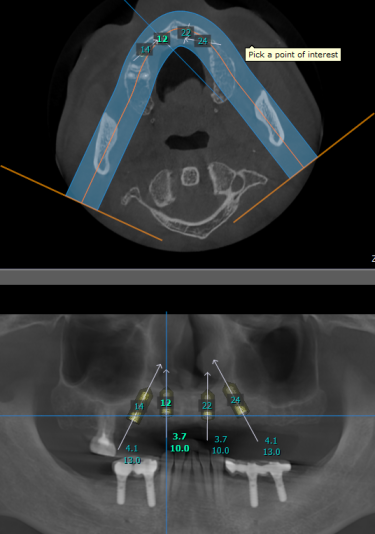

Good day to everyone, recently a gentleman came to my practice, requesting for implants to replace his upper non retentive complete denture. After taking the CBCT, i noticed that the remaining alveolar bone width and height are just sufficient for the all on 4 concept based on literature (5mm width and 10mm height). My surgical plan is as follows

2. Ridge expansion at planned implant site with densah bur and placement of 2 units 3.7x10mm at the anterior and another 2 units of 4.1x13mm implant at the posterior region followed by bone grafting with Ethoss. Temporisation with printed resin prosthesis.